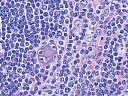

Multiples Myelom

Erkennbar sind dicht gepackte plasmazytoide Tumorzellen.